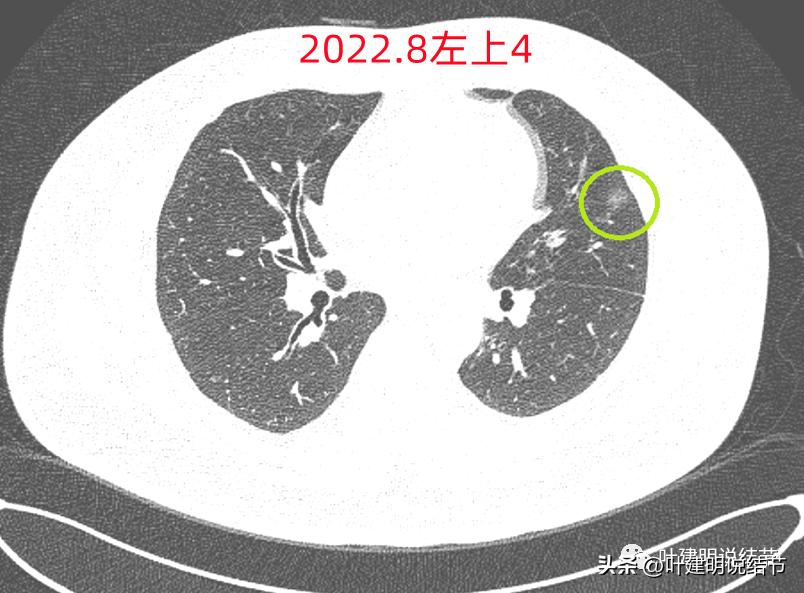

左上病灶4:舌段磨玻璃结节,边缘显力糊,整体轮廓较清,不典型增生可能性大点。

左上病灶4:

病灶出现,是淡磨玻璃影,但有微血管进入(桔色箭头)

密度稍不均,中间点状偏高密度,是不是血管?

周围微小血管好像有往病灶集中的趋势(桔色箭头)

病灶有胸膜间隙征(黄色箭头)、细毛刺样征(紫色箭头),整体轮廓较清(红色箭头)

轮廓清而密度稍不均,但总体仍应该算纯磨玻璃密度

有明显的血管穿行与细毛刺征

这个病灶也仍考虑是恶性范畴的,只是风险较病灶2与病灶3为低。也就是说看了细节与所有层面的信息,仍基本上认为四个病灶都是肿瘤范畴的,病灶1与病灶4大概浸润前病变可能性大,病灶2与病灶3则至少微浸润,基本以浸润性腺癌可能性大,不过不太能理解的有两点:一是病灶太集中;二是有的层面似有卫星灶。当然病灶2与病灶3感觉磨玻璃的成分偏少了些,也可作为疑惑之处。

但左上病灶4仍在,形态也没有明显变化,无好转,也无明显进展。这是肿瘤性质的吗?虽然存在2年多了,但因为它的兄弟们都不见了,让我对它认定的肿瘤范畴也产生了怀疑,也许是纤维增生而已呢!